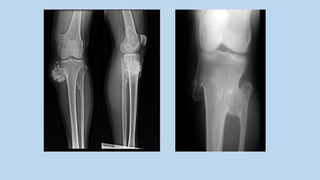

AP XR showing a proximal

tibial GCT.

Note the eccentric subarticular

location.*

Coronal T2WI showing a distal femoral GCT

with predominantly low SI due to haemosiderin

deposition from chronic haemorrhage.